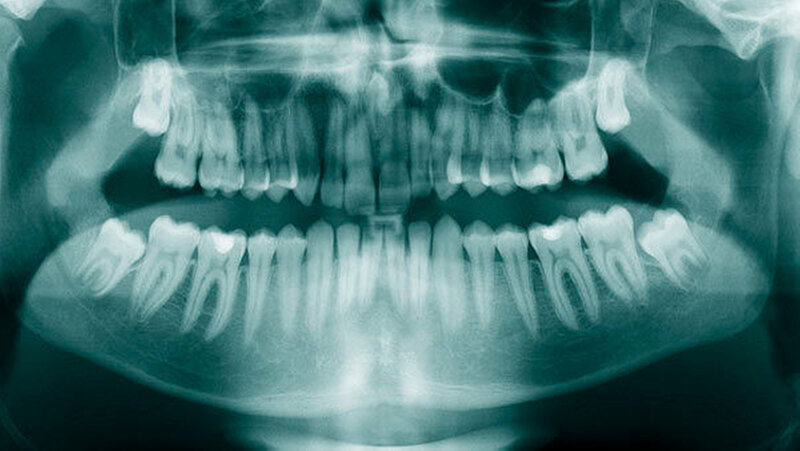

Überzählige Zähne sind die häufigste Ursache für einen unterbliebenen oder verzögerten Durchbruch der oberen Schneidezähne (Abbildungen 13, 14, 15) [Betts Camilleri, 1999]. Besonders beim höckerförmigen Typ kommt es häufig zu Störungen der Eruption der oberen Schneidezähne [Mason et al., 2000]. Diese Komplikation macht sich klinisch initial dadurch bemerkbar, dass die oberen seitlichen Schneidezähne durchbrechen und die Eruption von einem oder beiden zentralen Schneidezähnen ausbleibt [Rajab Hamdan, 2002]. Auch in anderen Lokalisationen der Kiefer können überzählige Zähne zu Durchbruchsstörungen benachbarter Zähne führen [Garvey et al., 1999; Rajab Hamdan, 2002; Mossaz et al., 2014]. Insgesamt liegt die Prävalenz für den Ausfall des Durchbruchs bleibender Zähne bedingt durch überzählige Zähne zwischen 10,2 Prozent und 61 Prozent [Tay et al., 1984; Koch et al., 1986; Tyrologou et al., 2005; Fernández Montenegro et al., 2006; Liu et al., 2007; Gündüz et al., 2008; Hyun et al., 2009; Mínguez-Martinez et al., 2012; Mossaz et al., 2014].

Überzählige Zähne werden nach ihrer Lage im Zahnbogen und auch aufgrund ihrer Morphologie eingeteilt. Basierend auf der Lage unterscheidet man bei überzähligen Zähnen zwischen Mesiodens (Oberkiefer median), zwischen den zentralen Inzisiven (Abbildungen 5 und 6), einem zusätzlichen Schneidezahn (zentral oder lateral), Eckzahn, Prämolar (Abbildung 7), Paramolar und Distomolar (Abbildungen 8). Mesiodentes werden am häufigsten dia- gnostiziert, wobei Prozentsätze zwischen 38,8 Prozent bis 86,3 Prozent der überzähligen Zähne in der Literatur zu finden sind [Salcido-García et al., 2004/38,8 Prozent, Fernández Montenegro et al., 2006 /46.9 Prozent; Mossaz et al., 2014/48.5 Prozent; Ferrés-Padró et al., 2009/53.2 Prozent; Schmuckli et al., 2010/75 Prozent; Rajab Hamdan 2002/83.2 Prozent; Liu et al., 2007/86.3 Prozent]. Überzählige Prämolaren und seitliche Schneidezähne sind die zweithäufigste Gruppe der überzähligen Zähne. Überzählige Eckzähne, Paramolaren und Distomolaren dagegen gelten als eher selten [Rajab Hamdan, 2002; Salcido- García et al., 2004; Liu et al., 2007; Ferrés-Padró et al., 2009; Schmuckli et al., 2010; Mossaz et al., 2014]. Einzig eine Spanische Gruppe [Fernández Montenegro et. al., 2006] berichtete, dass Paramolaren und Distomolaren insgesamt relativ häufig seien (18 Prozent, beziehungsweise 5,6 Prozent). Überzählige Zähne kommen im Ober- und Unterkiefer vor, wobei sich überzählige Schneidezähne in der Regel im Oberkiefer, überzählige Prämolaren sich dagegen eher im Unterkiefer befinden [Fernández Montenegro et al., 2006; Ferrés-Padró et al., 2009; Mossaz et al., 2014]. Überzählige Molaren wiederum treten normalerweise im Oberkiefer auf [Cassetta et al., 2014; Kaya et al., 2014].